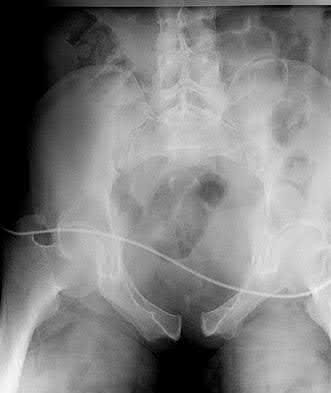

A 76-year-old male community ambulatory presented to clinic complaining of pain in the left groin that has been persistent for the last 8 months. Radiographs obtained from clinic are seen in Figure A. You suspect a femoral neck nonunion and obtain a CT scan which confirmed it. Which of the following statements is true?

A total hip arthroplasty (THA) after nonunion of a femoral neck fracture would provide the best long term outcomes in a 76-year-old male who is a community ambulator.

After nonunion of a femoral neck fracture, hemiarthroplasty and THA are good salvage option for the physiologically older patients. When deciding between these two options, THA is better for active and cognitively intact patients. THA is also indicated in patients with radiographic evidence of degenerative disease about the acetabulum. Hemiarthroplasty is advocated for patients who are older and less active.

Yang et al. retrospectively investigated the risk factors for nonunion in patients treated with cannulated screws. They reviewed 202 patients who had femoral neck fractures and were treated with internal fixation with cannulated screws. They identified that triangle configuration, displaced fracture, borderline or unacceptable reduction, and increased screw shaft subchondral purchase over the femoral neck were all risk factors for nonunion after internal fixation.

Inverted triangle configuration was found to increase rate of union.

Archibeck et al. retrospectively reviewed the outcomes of 102 THAs after failed internal fixation for a hip fracture (including both femoral neck and intertrochanteric). They concluded that the conversion of failed hip internal fixation has elevated risks compared to a primary THA, however, it may still be successful. The biggest concern for these patients postoperatively are periprosthetic fracture and dislocation.

Figures and Illustrations:

Figure A is an AP pelvic radiograph demonstrating a nonunion of a femoral neck fracture after suboptimal fixation with 3 cannulated screws in a triangle configuration.

Illustration A is an AP radiograph of the left hip in this patient following conversion to THA.

Illustration B is a radiograph demonstrating a valgus osteotomy. Illustration C shows an example of a femoral neck nonunion with varus malreduction.